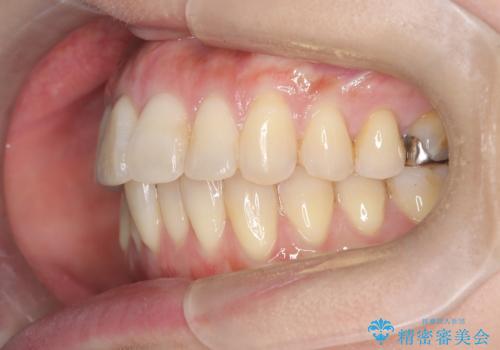

半年で改善した上顎前歯の突出

- 患者様は、上顎前歯の突出を改善したいとのご希望で来院されました。診断の結果、噛み合わせや全体的な歯列には大きな問題がないため、上顎のみを対象とした部分矯正が最適と判断しました。特に患者様は短期間での治療完了を希望されていたため、治療期間を約半年と設定しました。審美ワイヤーを用い、前歯を後方に移動させることで、自然で整った仕上がりを目指しました。治療計画は、患者様のスケジュールや希望を最大限考慮し、実現可能な目標を設定しました。

部分矯正では、治療範囲が限定されるため、力のコントロールが非常に重要です。本症例では、前歯を後方に移動させる際、周囲の歯や噛み合わせに影響を及ぼさないように細心の注意を払いました。また、短期間の治療でも歯の移動に伴う歯肉や歯根への負担を抑えるため、定期的なチェックと調整を行いました。患者様には矯正装置の清掃を徹底していただき、虫歯や歯周病のリスクを回避しました。結果として、予定通りの期間で治療を完了し、患者様には満足していただけました。